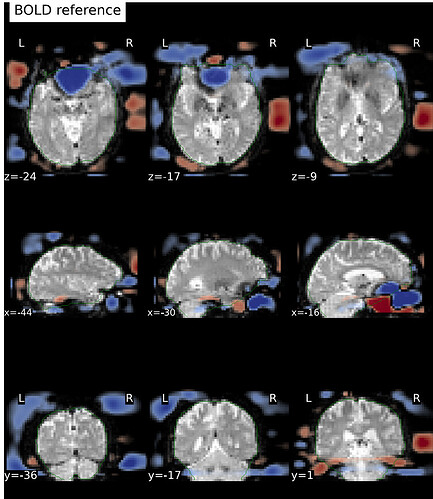

I’ve run fMRIprep 24.1.0 on ~ 150 datasets (PE-dir: func/RL_bold;fmap/LR_epi), and I noticed that for one of the subjects, the EPI and the reference fieldmap are not aligned well with each other.

Which appears as a signal-void region, affecting LR_epi (one top) and RL_bold (two bottom) differently: